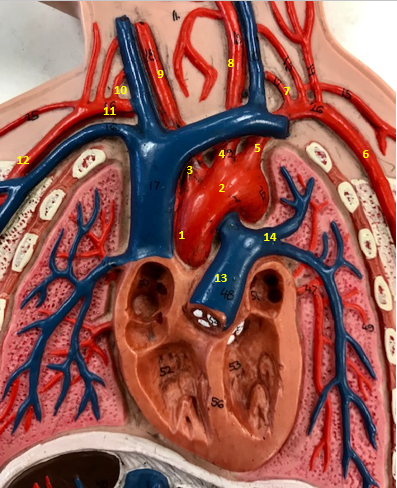

Aorta

Name #2

Brings blood out of left ventricle

Function of aorta

Brachiocephalic artery

Name #3

Supplies oxygenated blood to right arm shoulder neck and head

Function of brachiocephalic artery

Left common carotid artery

Name #4

Supplies oxygenated blood to left neck and head

Function of left common carotid artery

Left subclavian artery

Name #5

Supplies oxygenated blood to left arm shoulder

Function of left subclavian artery

Left axillery artery

Name #6

supplies blood to left armpit and upper limb

Function left axillary artery (6)

Left vertebral artery

Name #7

Supplies blood to brain and spinal cord

Function of left vertebral artery (7)

Left common carotid artery

Name #8

Supplies blood to left neck and head

Function of left common carotid artery (8)

Right common carotid artery

Name #9

Supplies oxygenated blood to right neck and head

Function of right common carotid artery (9)

Right vertebral artery

Name #10

Supplies blood to brain and spinal cord

Function of right vertebral artery (10)

Right subclavian artery

Name #11

Supplies blood to right arm and shoulder

Function of right subclavian artery

Right axillery artery

Name #12

Supplies blood to right armpit and upper limb

Function of right axillery artery (12)

Pulmonary trunk

Name #13

Bring blood out of right ventricle to lungs

Function of pulmonary trunk (13)

Left pulmonary artery

Name #14

Bring blood to left lung

Function of left pulmonary artery (14)